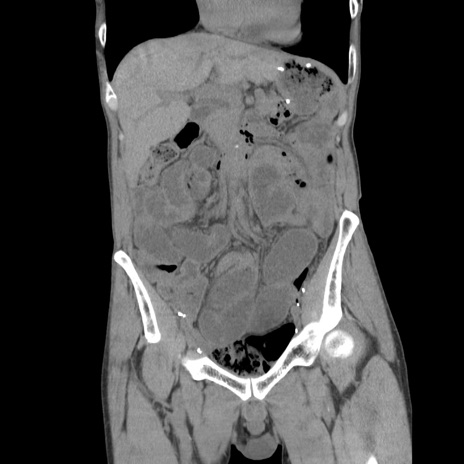

症例11(冠状断像)

【症例】 60歳代男性

【主訴】 下腹部痛

【現病歴】 本日夜中より下腹部痛の症状認め、受診。

【既往歴】 膀胱癌(膀胱全摘+尿管皮膚瘻術) 、胃癌術後

【身体所見】 BT 35.3℃、PR 58/min、BP 136/98mHg、腹部平坦、軟、腸蠕動音±、ストマ留置あり、左上腹部~正中部に圧痛あり、反跳痛なし。

【データ】WBC 5100、CRP0.01